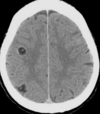

Size of tissue cysts in cysticercosis? where are they found?

A

1-2cm

Muscle (palpable) - eventually form calcified streaks

brain - seizures

7

Q

Most common cause of non-epileptic seizures worldwide

Neurocysticercosis